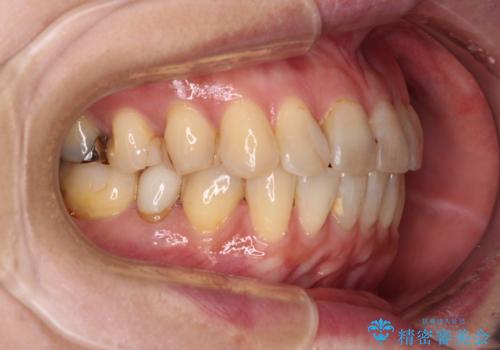

- 矯正装置

- 審美装置

- 前歯のデコボコを気にして来院された患者様です。

舌突出癖により、上下前歯がなかなか接触せずに治療期間を要しましたが、舌のトレーニングにより無事に治療を終えることができました。